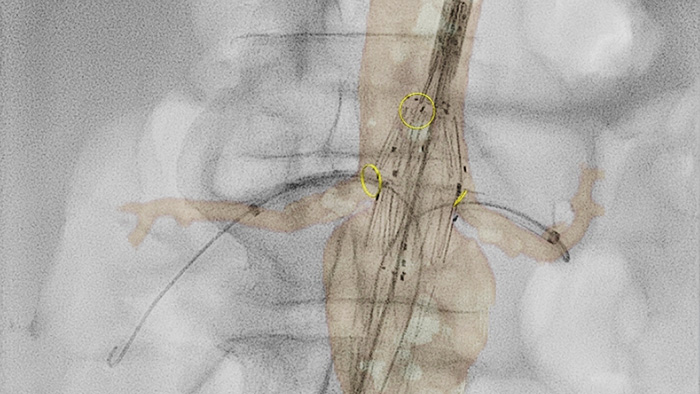

VesselNavigator

VesselNavigator ermöglicht die Wiederverwendung von dreidimensionalen Gefäßanatomiedaten aus bestehenden CTA- und MRA-Datensätzen als 3D-Roadmap-Überlagerung auf einem Echtzeit-Röntgenbild. Dank der hervorragenden Darstellung kann VesselNavigator kontinuierlich eine intuitive 3D-Roadmap als Führungshilfe bei der Navigation durch Gefäßstrukturen bieten.